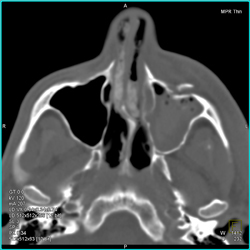

Normal Jugular Veins